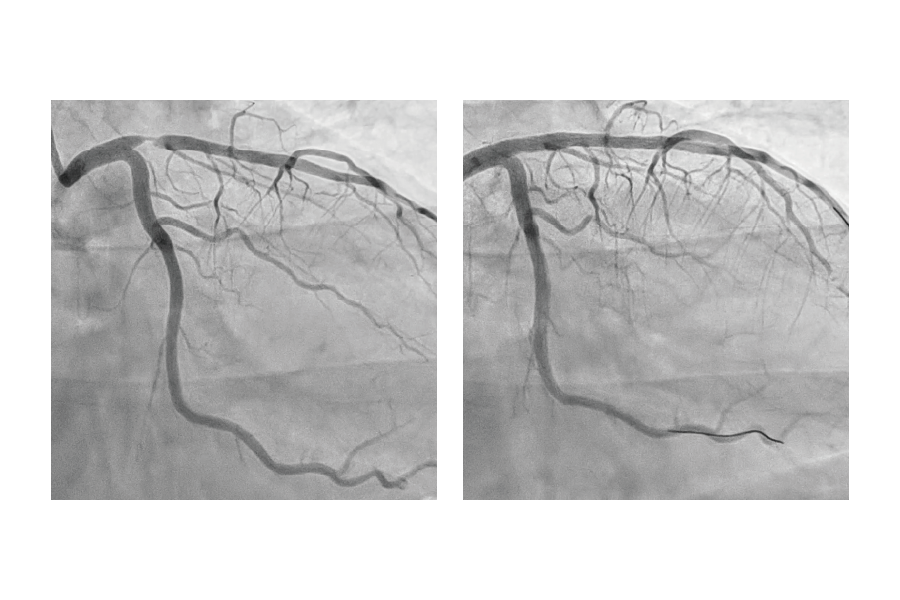

■急性心筋梗塞

BEFORE

AFTER

別疾患で入院中だった患者様が急性下肢閉塞を起こしましたが、

速やかな治療で改善し、2 日後に退院しました。